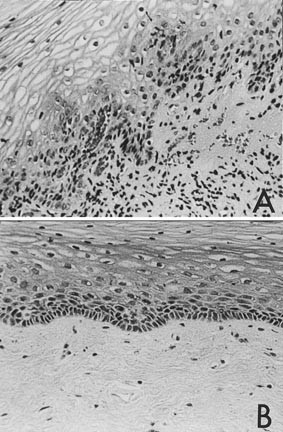

HIV-seropositive tissues overall showed more inflammation than seronegative controls (Fig. 1). Certain biopsies showed a psoriasiform pattern of inflammation, with blood vessel extension into the epithelial layer. Twenty of twenty-four vaginal biopsies (83.3%) from HIV-seropositive cases revealed inflammation Grade 2 and higher (see Table 2), whereas only five of twenty-four (20.8%) specimens from HIV-seronegative cases demonstrated the same degree of inflammation and the rest showed minimal or no inflammation.

Histologic appearance of vaginal mucosa. The degree of inflammation varied from site to site in individual patients but tended to be more severe in HIV-positive individuals. Illustrated here are A, the more severe degree of inflammation in an asymptomatic seropositive case showing diffuse lymphocytic infiltration of the lamina propria with extension into the epithelium and B, the opposite end of the spectrum in a seronegative case showing no inflammation (both H&E, 200 ×).